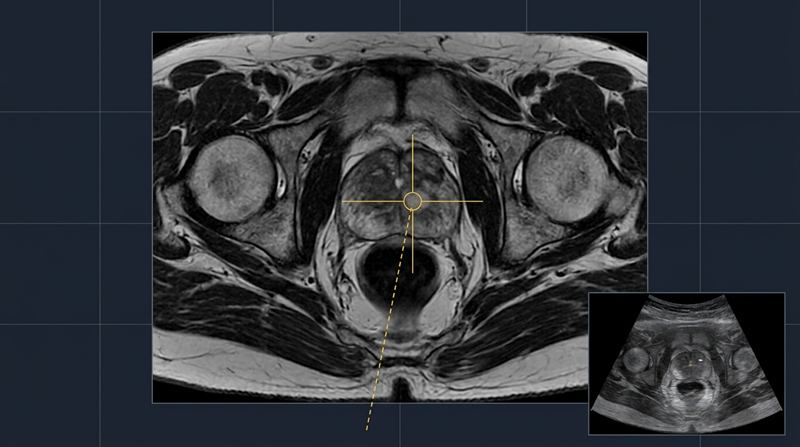

MRI-Guided Transperineal Biopsy

Dr Kooner is one of the first in Australia to perform transperineal ultrasound-fusion guided biopsy into the prostate. This technology allows more accurate biopsy with fusion of MRI abnormalities onto ultrasounds used in theatre. This then allows the abnormalities to be targeted more accurately7.